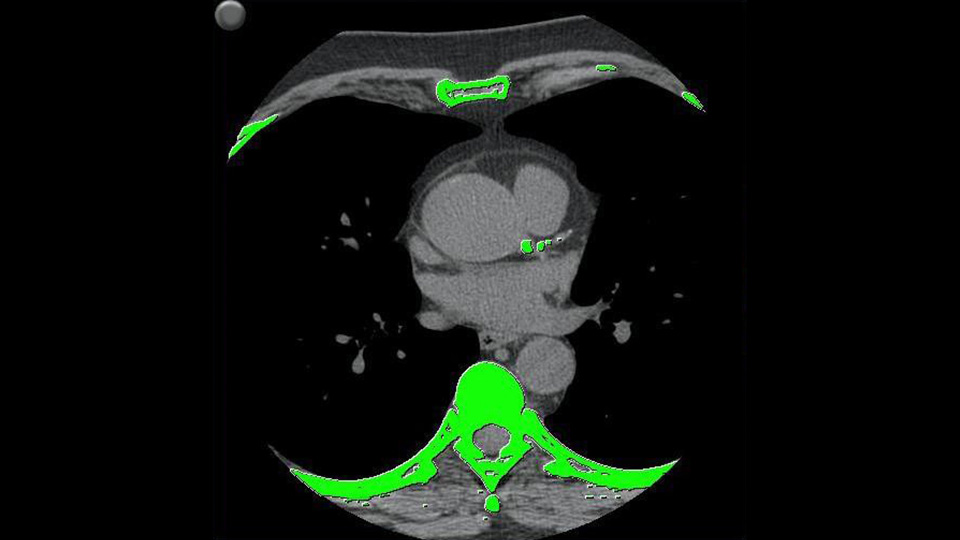

SmartScore 4.0

SmartScore 4.0 is designed to identify the presence of regional and global coronary artery calcification from a CT scan, then measure and score the results.